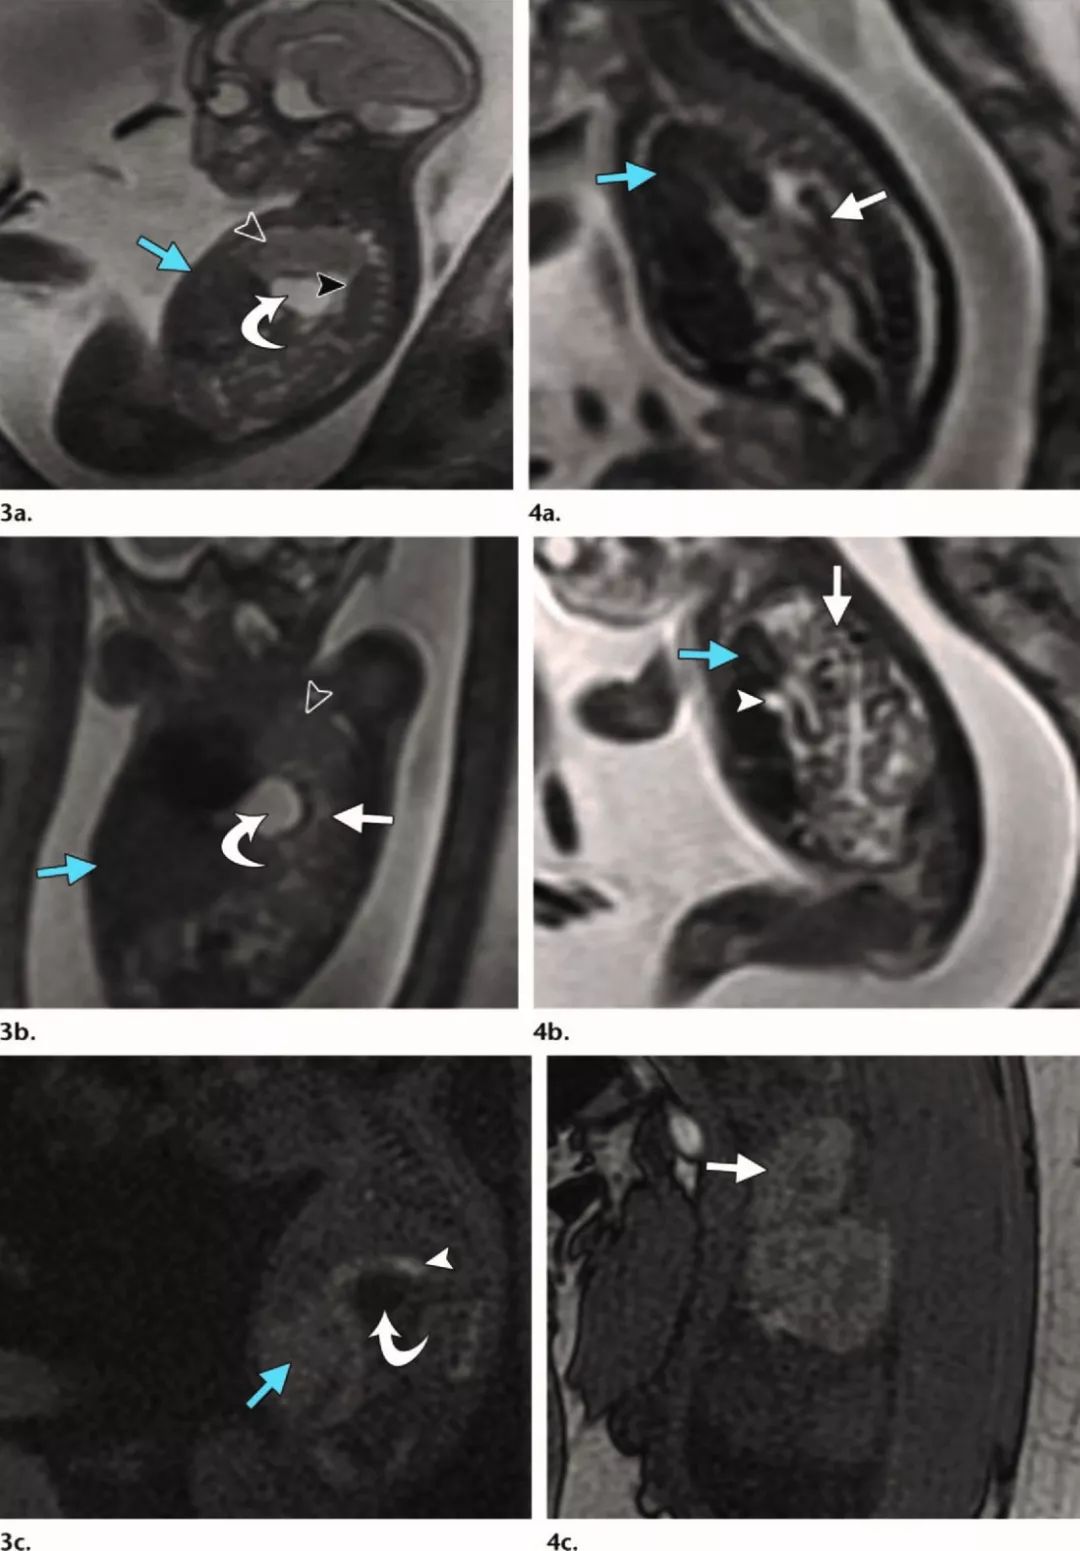

图

3

、

4. (3)

左侧

CDH

,妊娠

21

周。矢状位(

a

)和冠状位(

b

)

SSFSE T2WI

和矢状位

T1W

梯度回波图像(

c

)显示胃疝(

a-c

,曲箭)、肠疝(

b

,直白箭)和脾疝(

a

,黑箭头)伴左肺发育不良(

a

、

b

,空箭头)。未见肝左叶疝(

a-c

,蓝箭)。图

c

显示肝左叶位于膈下位置、胃疝和结肠脾曲(箭头)。相对肺容量

48%

。(

4

)右侧

CDH

,妊娠

22.5

周。

(a

,

b)

矢状

SSFSE T2W

图像显示肝右叶疝

(

蓝色箭

)

、胆囊疝

(b

,箭头

)

和肠袢疝

(

白色箭

)

并到达右半胸的上三分之一。(

c

)冠状位

T1W

梯度回波图像显示肝右叶疝(箭)。相对肺容量

33%

。